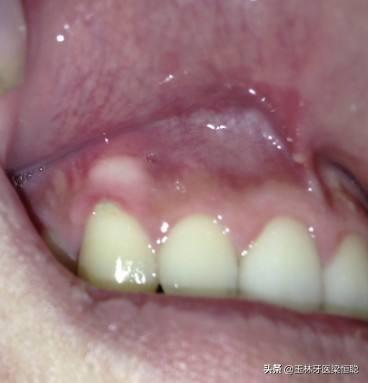

臨床上,我們常常遇到患者說“牙齦上鼓了個(gè)包,硬硬的”,或鑲牙的老人說“牙床壓著疼”,通??赡苁浅霈F(xiàn)了牙槽骨骨質(zhì)增生。

口腔內(nèi)牙槽骨的骨質(zhì)增生是指牙齦區(qū)域的牙槽骨出現(xiàn)骨質(zhì)增生性突起,在臨床上比較常見。

骨質(zhì)增生的形式多種多樣,因所在部位不同而有其各自的特點(diǎn),在口腔中多表現(xiàn)多圓錐狀突起或小骨刺,一般沒有的臨床癥狀,有時(shí)候伴有輕微的疼痛,可以通過X光攝片清晰地辨認(rèn)骨質(zhì)增生的部位和增生的程度。